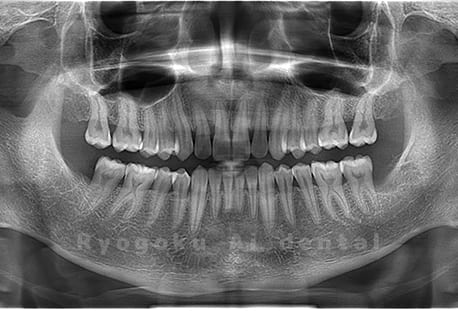

Case03

- 原因

- 上顎、下顎の親知らず

- 治療内容

- 上下4本の親知らずを抜歯したケースです。

<リスク・副作用>

手術後は痛み、腫れ、痺れなどの副作用が生じる場合があります。